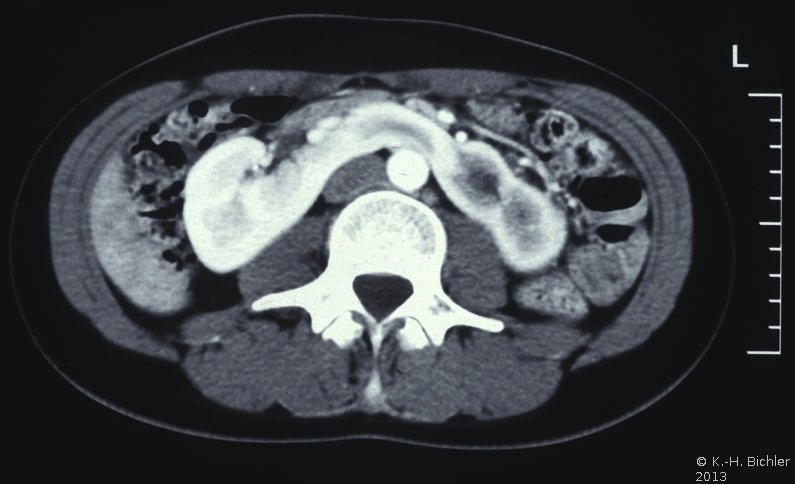

In der Sonographie und im i.v.-Pyelogramm sind malrotierte Nieren beidseits wegweisend. Sonographisch kann der Isthmus nachgewiesen werden. In unklaren Fällen bzw. bei Komplikationen kann mit der Computertomographie der Isthmus, der sich meist in Höhe von Lendenwirbelkörper 3 und 4 befindet, gesehen werden (Abbildung 2).